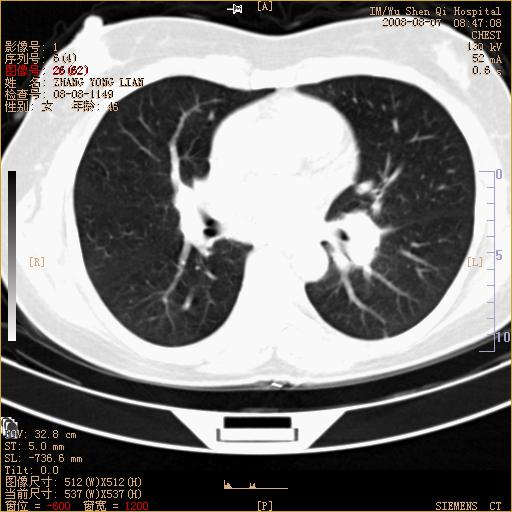

标题: CT15050:女,46岁,咳嗽胸痛一月余 [打印本页]

纵隔窗没发全,左下肺近胸膜处结节。有长毛刺,纵隔淋巴结增大,不排除恶性病变。

考虑左肺下叶后基底段周围型肺癌伴纵隔淋巴结转移可能性大。

左下肺ca并纵隔及左肺门区淋巴结转移。

脾脏低密度结节转移不排除。

1)考虑左肺下叶后基底段周围型肺癌伴纵隔淋巴结转移。2)脾内低密度灶,性质待定;不排除转移瘤可能。

恶性度很高的肺癌.